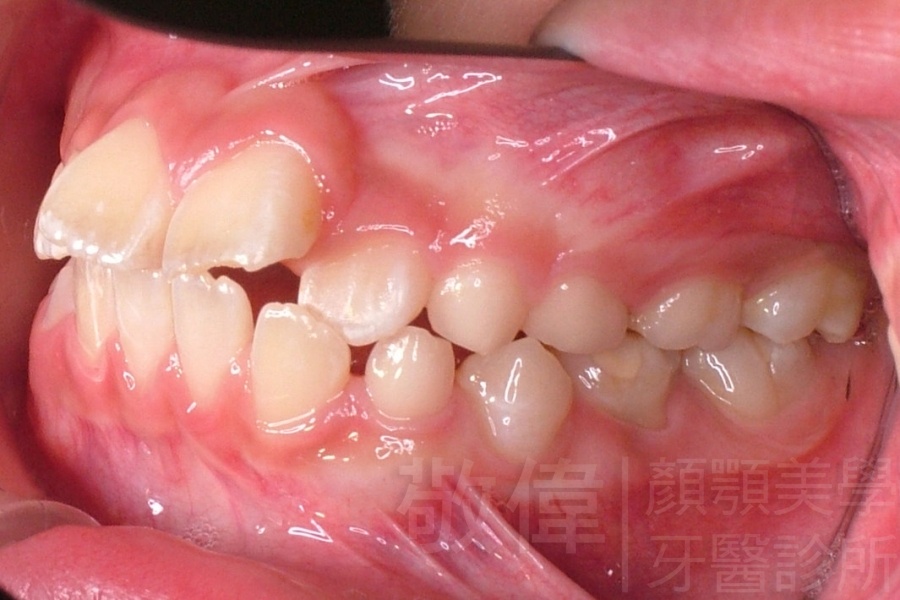

齒顏矯正/上顎暴牙且牙齒極度混亂

矯正前-右   矯正前-正   矯正前-左

矯正前-上   矯正前-下

<個案說明>

上顎暴牙且牙齒極度混亂,經由矯正之後,臉型大幅度改善,牙齒的排列更加的整齊健康。相較於之前眼神充滿精神,自信心展現無遺。